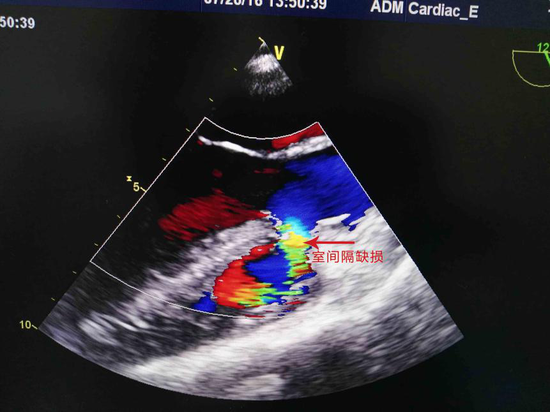

心脏彩超诊断报告单,心脏彩超报告单

心脏彩超

心脏彩超不正常图片

正常心脏彩超图片

心脏彩超图片

心脏彩超图片图谱

心脏彩超图片图解